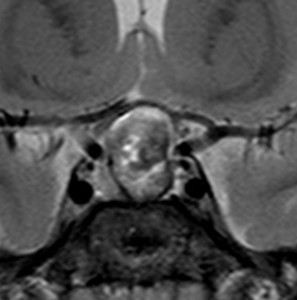

多少取り残しても再発しない

29歳の女性が高プロラクチン血症による月経不順で発症しました。視野検査では両耳側半盲が認められました。

手術所見では,多量のコレステリン結晶が流出しました。腫瘍実質は硬く正常下垂体との剥離はできませんでした。黄色肉芽種の可能性もあるので,あ全摘出にとどめて手術を終了しました。T2強調画像で黒い低信号の縁取りがあり内部に不均一なのう胞内容液が見えるのが特徴とも言えます。

3年後の画像です。腫瘍の再燃増大はありませあん。視野は正常化して,下垂体機能も正常化しホルモン補充はありません。